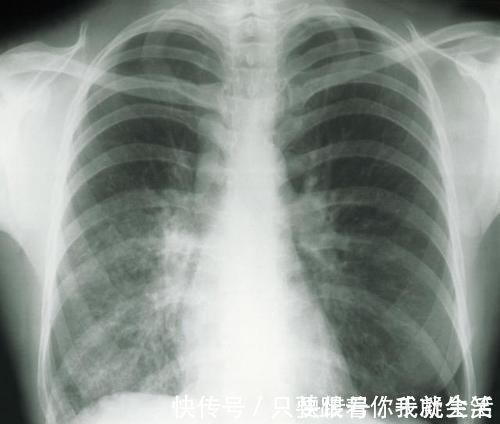

随着人们生活水平和健康意识的提高,期体检已成为常规。当拿到体检报告时,很多人都为报告上的肺部有\\\"磨玻璃影”字样而纠结不已。患者陈女士就是一个典型的例子。

两年前,陈女士在体检中意外查出肺结节,且双肺多发,这让有肺癌家族史的陈女士慌了神。

近期,陈女士来到医院复查,薄层CT扫描结果显示,陈女士左肺为磨玻璃结节,且有增大现象,考虑恶性可能度高。

术后病理结果显示,陈女士体内的肺结节,最大的仅有0.9cm,但已发展为早期浸润肺癌,一个为原位腺癌,0.4cm,其他的均为炎症性结节。

肺磨玻璃结节一般是在做胸部CT时发现,表现为密度轻度增高的云雾状淡薄影或圆形结节,样子像磨砂玻璃,所以叫磨玻璃影。可以是弥漫性散在生长,也可以聚集在局部,看起来就像一个小磨玻璃结节。